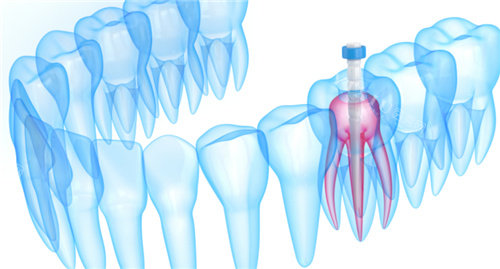

种植牙:采用国内外可靠的种植系统,结合智能化导板技术,实现比较准、小创口的种植修复

口腔显微镜:放大视野,确保治疗比较准度